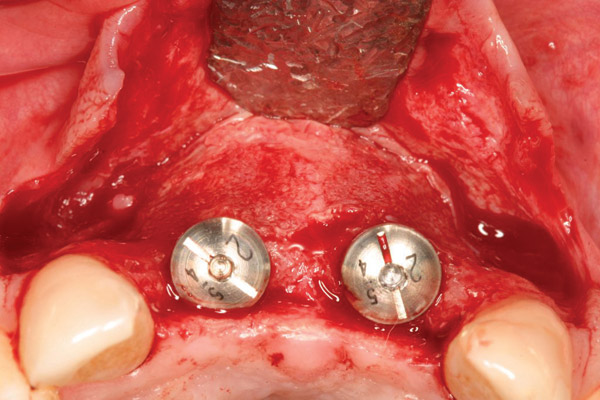

Figure 15  After extraction and 3 months of healing, two implants were placed in ideal position and with primary stability at sites Nos. 8 and 9. Implants were stable. Dehiscence defects exposing 13 threads were produced.

Figure 15

Figure 20  At the second-stage surgery following a healing period of 5 months, temporary healing abutments were placed. This occlusal view shows complete regeneration of the labial plate of bone.

Figure 20